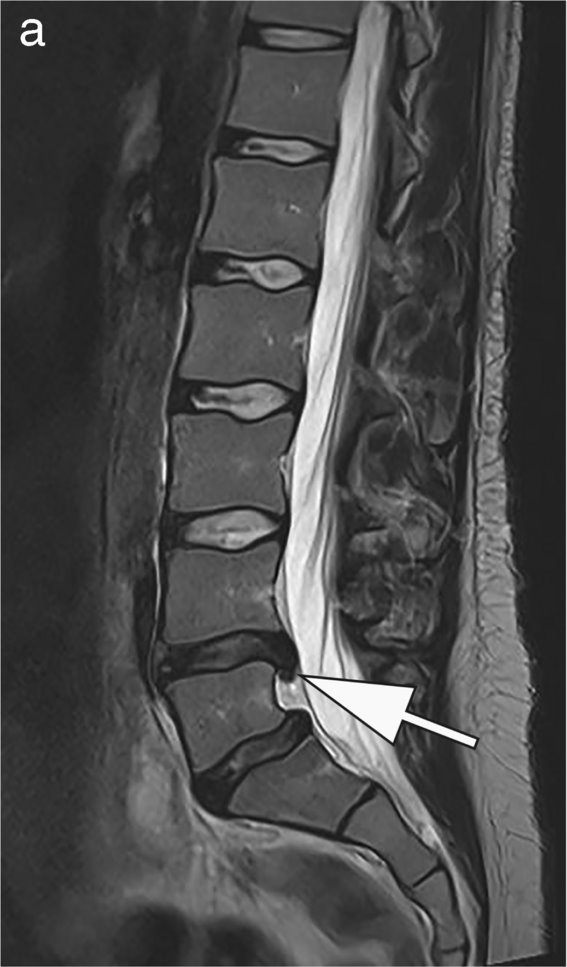

Image source: Pogarell T, Heiss R, Janka R, Nagel AM, Uder M, Roemer FW, Skeletal Radiology 2024 (CC BY 4.0)

A complement, not a replacement

Vilanova insists low-field MRI is not intended to replace high-end systems. ‘We still need 3T for advanced exams – cardiac, breast, functional neuro,’ he said. ‘But low-field should be used strategically, to offload high-field units and improve workflow.’

At ESMRMB 2026 in Girona, low-field applications will take center stage again – not just as a technology, but as a tool for rethinking resource allocation in radiology. ‘Low-field is clinically relevant, cost-effective, and sustainable,’ Vilanova concluded.